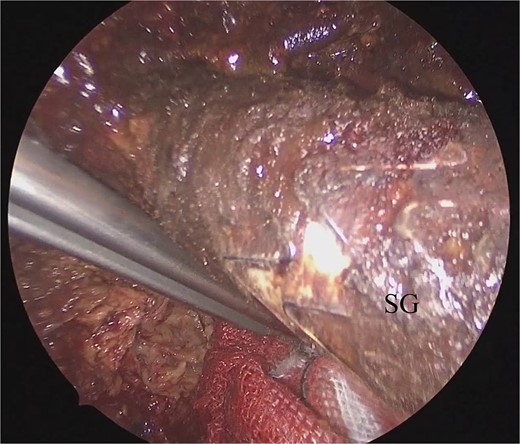

He underwent surgery under general anesthesia. A midline abdominal incision and an intraperitoneal approach were employed. Due to the aneurysm’s size, combined with adhesions to the surrounding intestines and the thinness of the aneurysm wall, achieving complete exposure was particularly challenging. Therefore, the aneurysm was incised midway. The hematoma and coils were removed, and the feeding vessels were ligated with 3–0 monofilament. Blood oozing from the feeding vessels suggested that the aneurysm expansion was likely due to a type II endoleak that was not visible on contrast-enhanced CT. The laparoscope was used to observe the aneurysm, identify, and ligate the inflow vessels that were difficult to visualize directly (Fig. 2). The IIA was sutured with 3–0 monofilament using laparoscopic assistance, taking care to avoid including adjacent structures such as the rectum in the sutures. The operation took 255 min, and the patient was discharged on the fourteenth day postoperation. Follow-up CT at 10 months postoperation showed a reduction in aneurysm size (Fig. 3).

Laparoscopic view of the orifice of the feeding vessel (blue arrow).